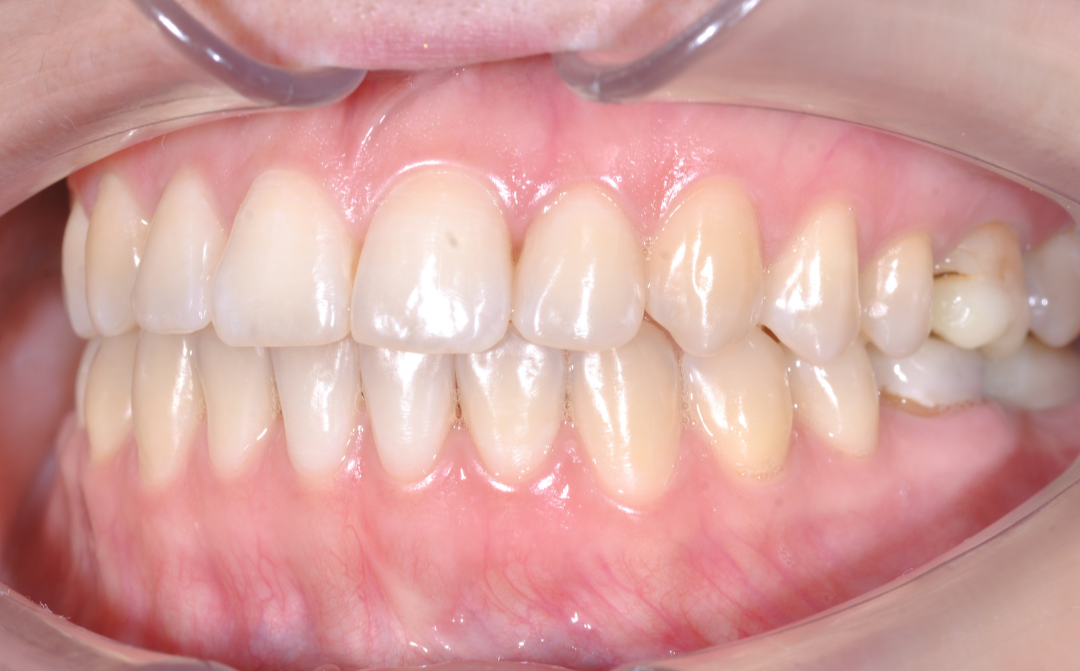

После

Здоровая улыбка

Ушел дискомфорт в суставе, исчезли боли в процессе жевания. Нижняя челюсть заняла стабильное, физиологичное положение.

Восстановилась функция

Качество жевания кардинально повысилось, процесс приема пищи снова стал комфортным.

Эстетика

Исправлен прямой прикус, восстановлена форма резцов, а улыбка стала не только красивой, но и здоровой с точки зрения биомеханики.